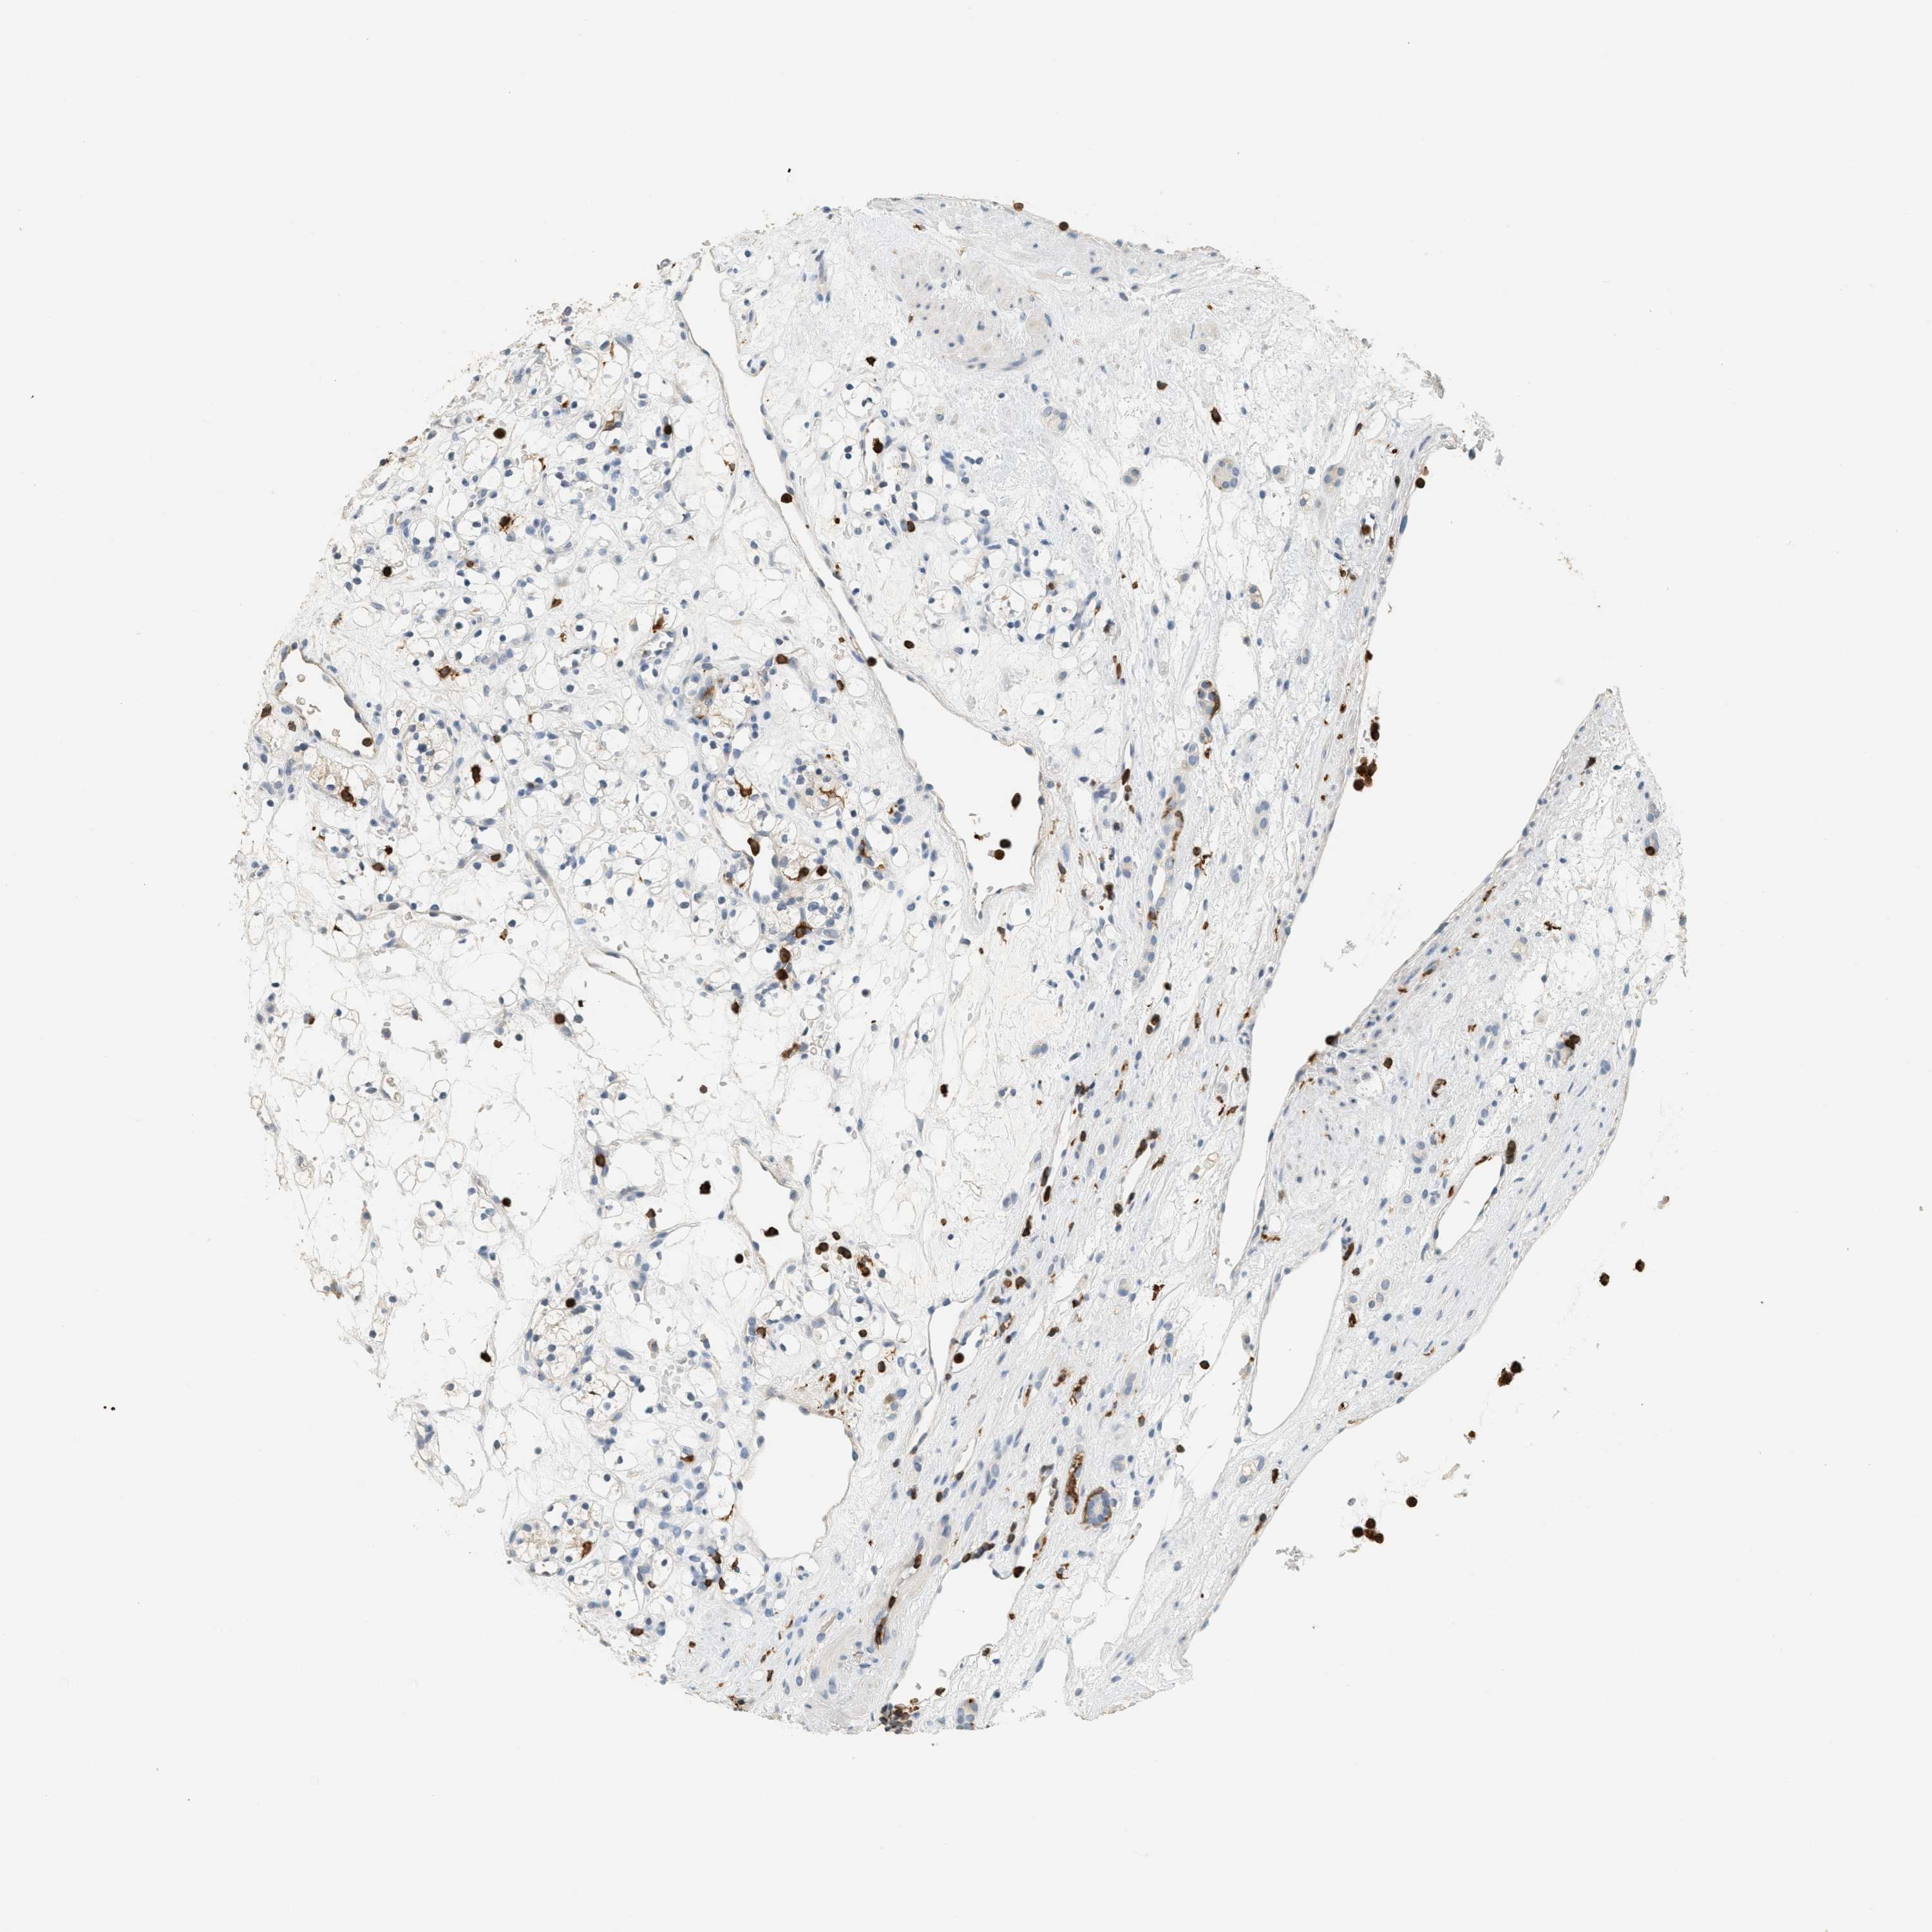

KIDNEY RENAL PAPILLARY CELL CARCINOMA (TCGA) - Interactive survival scatter ploti

The Survival Scatter plot shows the clinical status (i.e. dead or alive) for all individuals in the patient cohort, based on the same data that underlies the corresponding Kaplan-Meier plots. Patients that are alive at last time for follow-up are shown in blue and patients who have died during the study are shown in red.

The x-axis shows the expression levels (FPKM) of the investigated gene in the tumor tissue at the time of diagnosis. The y-axis shows the follow-up time after diagnosis (years). Both axes are complimented with kernel density curves demonstrating the data density over the axes. The top density plot shows the expression levels (FPKM) distribution among dead (red) and alive patients (blue). The right density plot shows the data density of the survived years of dead patients with high and low expression levels respectively, stratified using the cutoff indicated by the vertical dashed line through the Survival Scatter plot. This cutoff is automatically defined based on the FPKM cutoff that minimizes the p-score. The cutoff can be changed by dragging the vertical line or by entering a cutoff value in the square labeled "Current cut-off".

Under the Survival Scatter plot the p-score landscape (black curve; left axis) is shown together with dead median separation (red curve; right axis). Dead median separation is the difference in median mRNA expression between patients who have died with high and low expression, respectively. It is calculated as follows: median FPKM expression of dead patients with high expression - median FPKM expression of dead patients with low expression. This is intended to aid the user in visually exploring custom cutoffs and the associated p-scores and dead median separation.

Individual patient data is displayed and can be filtered by clicking on one or more of the category buttons on the top of the page. Categories describing expression level and patient information include: high, low, alive, dead, female, male and tumor stages. The scale of the x-axis can be toggled between linear and log-scale by clicking on the "x log" button. Mouse-over function shows TCGA ID, patient information and mRNA expression (FPKM) for each patient.

& Survival analysisi

Kaplan-Meier plots summarize results from analysis of correlation between mRNA expression level and patient survival. Patients were divided based on level of expression into one of the two groups "low" (under cut off) or "high" (over cut off). X-axis shows time for survival (years) and y-axis shows the probability of survival, where 1.0 corresponds to 100 percent.

LSP1 is not prognostic in Kidney Renal Papillary Cell Carcinoma (TCGA)

Best expression cut offi